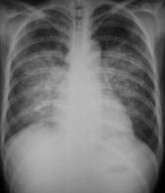

肺水肿间质期的X线表现主要为肺血管纹理模糊,增多,肺门阴影不清,肺透光度降低,肺小叶间隔增宽。两下肺肋膈角区可见与胸膜垂直横向走行的KerleyB线,偶见上肺呈弧形斜向肺门较KerleyB线长的KerleyA线。肺泡水肿主要表现为腺泡状致密阴影,呈不规则相互融合的模糊阴影,弥漫分布或局限于一侧或一叶,或从肺门两侧向外扩展逐渐变淡成典型的蝴蝶状阴影。有时可伴少量胸腔积液。但肺含量增加30%以上才可出现上述表现。CT和核磁共振成像术可定量甚至区分肺充血和肺间质水肿,但费用昂贵。

肺水肿2

• 肺纹理和肺门阴影边缘模糊。

• 肺血重新分布现象,即由正常时上肺血管比下肺血管细变为上肺野血管增粗。

• 支气管袖口征,支气管轴位投影可见管壁环形厚度增宽,边缘模糊,称为袖口征。

• 间隔线阴影,其病理基础是小叶间隔水肿。可分为KerleyA、B、C线,以B线最常见,长度小于2cm,与胸膜垂直。

• 胸膜下水肿,类似胸膜增厚,不随体位改变而变化。叶间胸膜下水肿表现为叶间裂增厚。

• 常合并心影增大。可有少量胸水

• 肺泡实变阴影,早期呈结节状阴影,约0.5-1cm大小,边缘模糊,很快融合成斑片或大片状阴影,有含气支气管影像.密度均匀。

• 分布和形态呈多样性,可呈中央型、弥漫型和局限型。中央型表现为两肺中内带对称分布的大片状阴影,肺门区密度较高,形如蝶翼称为蝶翼征。局限型可见于一侧或一叶,多见于右侧。除片状阴影外,还可呈一个或数个较大的圆形阴影,轮廓清楚酷似肿瘤

• 动态变化:肺水肿最初发生在肺下部、内侧及后部,很快向肺上部、外侧及前部发展,病变常在数小时内有显著变化。

• 胸腔积液:较常见,多为少量积液,呈双侧性。

• 心影增大。